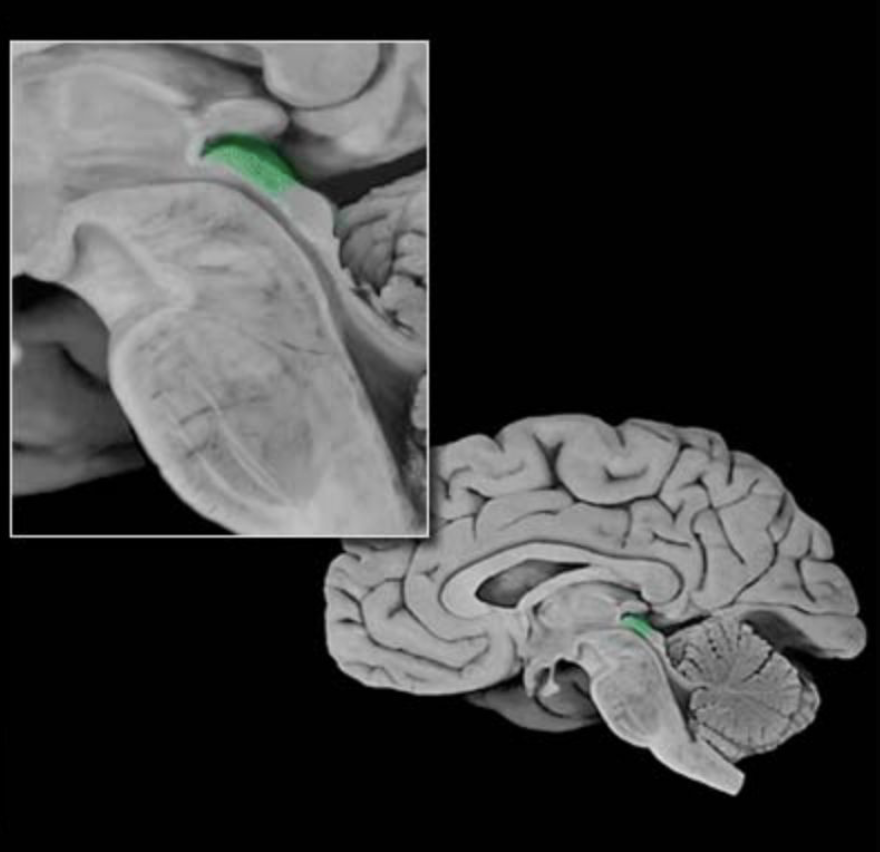

Red nucleus

Prominent nucleus located in the tegmentum of the rostral midbrain. Its major parvocellular (small-celled) division conveys signals from the cerebral cortex to the inferior olivary nucleus, which in turn modulates activity in the cerebellum. A minor magnocellular (large-celled) division may contribute to the control of the distal upper extremities via projections to the lateral ventral horn of the spinal cord, projections that form the rubrospinal tract; however, this projection is vestigial and variable in humans and its functional significance is uncertain.